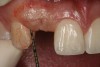

Figure 10  Clinical examination of the bound edentulous space: Measurement of the distal (Fig 10) and mesial (Fig 11) interproximal tissue height using a periodontal probe supplements data obtained from the periapical radiograph. Estimation of the buccal tissue thickness (bone sounding) is performed at the determined location of the gingival zenith using a guide developed from the diagnostic waxing (Fig 12).

Figure 10